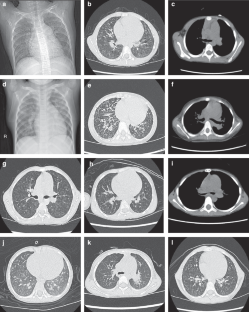

All patients had PH at diagnosis, with 64.7% (11/17) exhibiting moderate-to-severe pulmonary artery systolic pressure (PASP) elevation. Macrocytic anemia and renal dysfunction were common. HRCT revealed centrilobular ground-glass nodules, interlobular septal thickening, and pulmonary hemorrhage. B-type natriuretic peptide (BNP) levels were significantly higher in the moderate-severe group. All patients received metabolic therapy, and 11 received PH-targeted drugs. Glucocorticoids led to rapid clinical improvement in two patients presenting with pulmonary hemorrhage or hypoxemia. PASP normalized in all cases within 18 months. No recurrence occurred during follow-up.